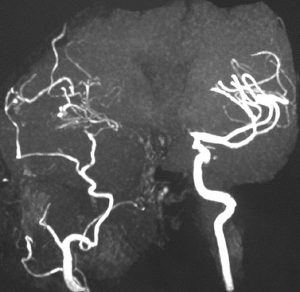

4歳の時に頭蓋咽頭腫に対して50グレイの分割照射を受けました。両側の内頸動脈と前交通動脈が被曝しています。16歳(12年後)に左片麻痺の虚血発作を生じました。右内頸動脈が閉塞してウィルス動脈輪閉塞(モヤモヤ病)になっていました。前交通動脈に動脈瘤(赤矢印)もできていました。小児の頭蓋咽頭腫への放射線治療ではかなり高率に閉塞性脳血管障害を生じるのですが,治療後10年以上がたってから起るので,治療を行った医師はそれをみることはほとんどありません。